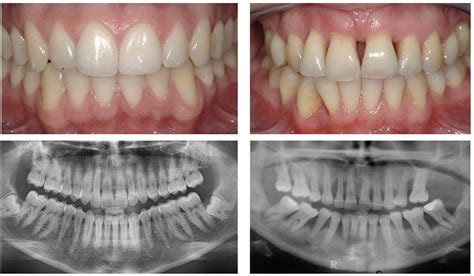

Periodontal disease is a silent, inflammatory condition that affects the tissues surrounding and supporting your teeth. It typically begins as gingivitis, characterized by inflammation, and can advance to periodontitis, which involves the destruction of bone and connective tissue. By examining Gum Disease Pictures, you can often identify the transition from healthy, firm, pink gums to tissues that appear puffy, red, or even receding.

When you look at resources providing Gum Disease Pictures, you will notice consistent visual markers. Recognizing these early is essential to preventing permanent tooth loss. The following table highlights what you should look for compared to healthy tissue:

Visual Indicator Healthy Gums Signs of Disease

Color Firm, pale pink Deep red, purple, or bright red

Texture Stippled (orange peel texture) Smooth, shiny, or puffy

Margin Snug against the tooth Receding or showing gaps/pockets

Bleeding None Frequent bleeding during brushing

The goal of looking at Gum Disease Pictures should be to reinforce positive habits. Reversing the early stages of gingivitis is entirely possible with consistent care, while managing advanced stages requires a partnership between you and your dental provider. Focus on these pillars of oral hygiene:

Ultimately, the key to avoiding the consequences depicted in Gum Disease Pictures lies in early intervention and daily vigilance. By paying attention to the color, texture, and position of your gum tissue, you can catch minor issues before they escalate into complex health challenges. Periodontal health is not just about avoiding bad breath or sensitive teeth; it is a foundational pillar of your systemic wellness. Adopting a proactive approach, including regular professional checkups and a disciplined home care routine, ensures that your smile remains healthy and your gum tissue stays firmly attached for years to come. Remember that your gums serve as the protective barrier for your jawbone, and keeping them healthy is an investment that yields lifelong benefits for your overall physical health.